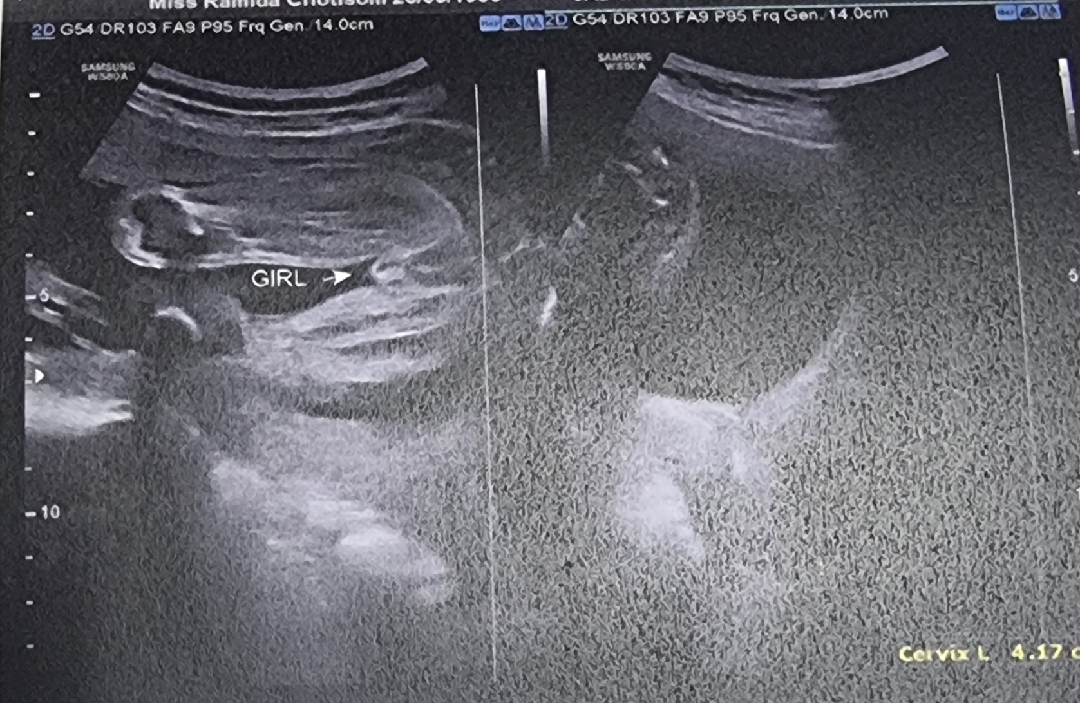

24 w น้ำหนักลูก 730 g

24 w น้ำหนักลูก 730 g แล้ว แม่ๆบ้านน้ำหนักน้องเยอะเหมือนบ้านนี้มั่งค่ะแชร์หน่อยได้ไหม คุณหมอบอกลูกตัวใหญ่จังคุณแม่ อาจจะได้ผ่าคลอด ไม่รู้แม่จะดีใจรึเครียดดี 😂😂😂